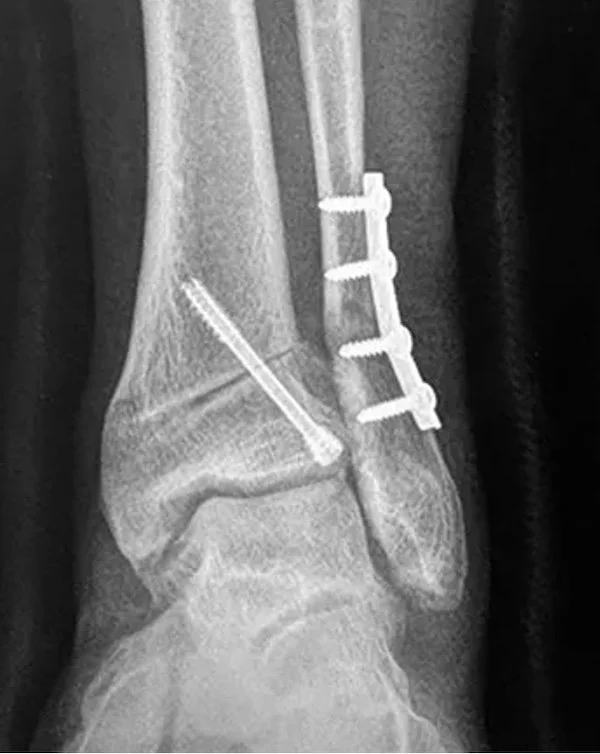

ARTHRODESIS ( JOINT FUSION )

Some conditions necessitate the removal of a joint. when we remove a joint one option is to attach the remaining bones to each other and to let them heal into one larger bone. This does stop any motion that the joint had before the surgery but when it comes to the foot or ankle that loss of motion may not be too noticeable to the patient. We perform fusions for situations where there is significant arthritis and cartilage damage in a joint that cannot be salvaged. Click here: ARTHRITIS SURGERY to learn more about other techniques we can use to avoid fusion. The good thing about arthrodesis or joint fusion is the fact that it works well in most cases without significant complications in most cases. (of course this depends on the skill and experience of the surgeon and the overall medical condition of the patient). The other good thing is that its outcomes are predictable- the fused joint should remain in the position that it was placed into. Another reason we use this fusion technique is to correct deformities like in the case of FLATFOOT or CLUBFOOT.

During the surgery , once the joint is prepared for fusion. Hardware must be placed - these surgical implants will hold the bones together while they heal into each other. The types of implants placed depend on the surgeons preference and on the procedure location. Screws , pins, plates or external scaffolds can be used for this.

A common question we get is : Does the screw need to be removed? answer is No unless it bothers the patient. The implants are usually buried deep into the bone and can stay inside.

What are these implants made out of? Modern surgical screws are usually made from titanium, occasionally some made from surgical stainless steel are used. Modern plates are made from either titanium or stainless steel. Also there are a few screws and pins that are available for the surgeon to use that are made out of an absorbing material- and yes over time they are absorbed by the body and disappear. ( not commonly used nowdays)